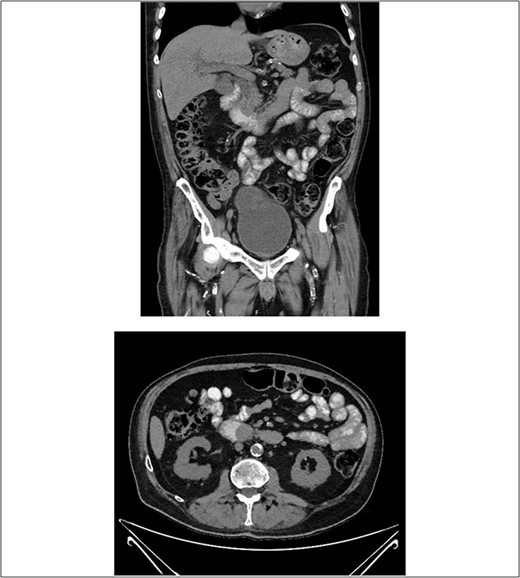

After consultation with our Hepatobiliary service, the consensus was for the patient to undergo an urgent ERCP. Intraoperatively, a duodenoscope was introduced through the mouth and was advanced to the duodenum at the ampulla of Vater. The major papillae were bulging and a malignant appearing infiltrative mass was visualized. A tapered tip cannula was inserted through the ampulla and contrast was injected, revealing a patent PD and a single 18-mm long stenosis of the distal third of the CBD with significant dilatation of the proximal CBD and intrahepatic ducts (Fig. 2). A 10Fr 7-cm transpapillary plastic stent was inserted with a single internal flap, 5.5 cm, into the CBD. The biliary pancreatic junction was biopsied with cold forceps for histology. Cholangiopancreatography revealed the stent was in good position with good flow of contrast into the duodenum beyond the filling defect (Fig. 3).

(A) and (B) malignant appearing soft tissue infiltrative mass within the ampulla of Vater seen on ERCP; (C) cholangiopancreatography showing stenosed distal third of the common bile duct along with a patent pancreatic duct.

(A) and (B) endoscopic images showing a single plastic stent inserted into the distal CBD, protruding into the second part of the duodenum; (C) position confirmed on cholangiopancreatography revealing resolution of distal CBD filling defect.